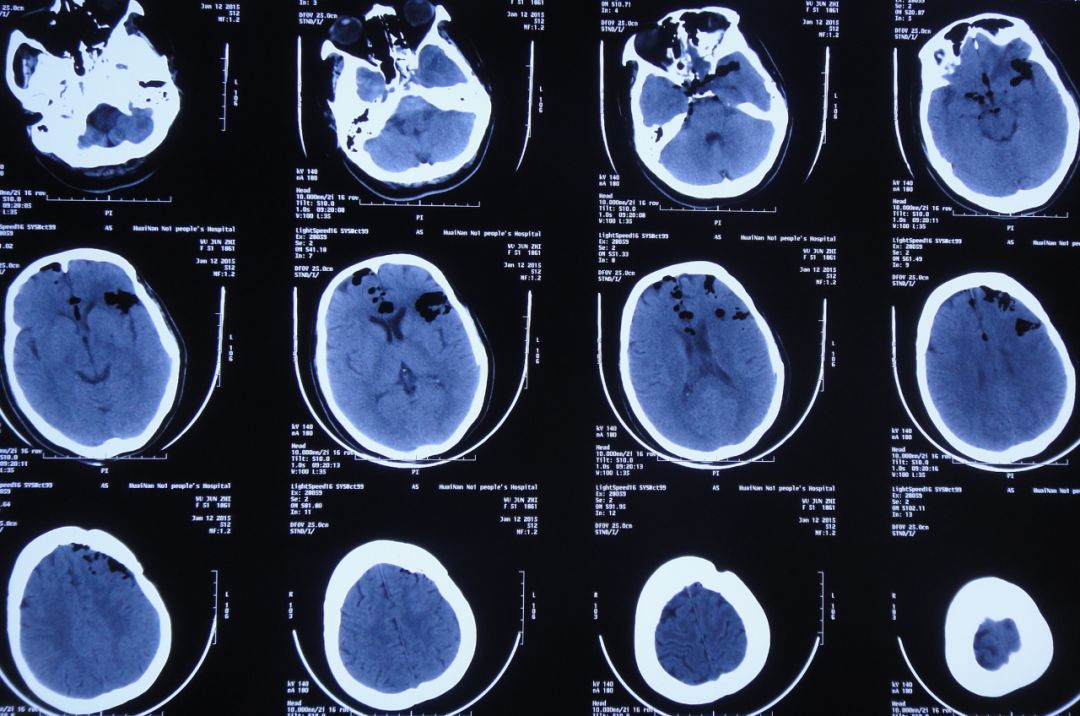

考虑患者仍存在脑脊液鼻漏;在开颅术后第40天即2015年9月22日,患者接受了“经鼻鼻内镜下脑脊液鼻漏修补术”(图23)。

图23:2015年9月22日患者行经鼻鼻内镜下脑脊液鼻漏修补术

术后当日复查头CT显示术区未见明显异常(图24)。

图24:2015年9月22日头CT:术区未见明显异常

患者术后第16天即2015年10月8日,患者神清,无明显不适,脑脊液呈淡黄色透明(图28);复查头CT:鞍区积气(图29)。

图28:2015年10月8日患者一般情况可,脑脊液呈淡黄色透明

图29:2015年10月8日头CT:头CT:鞍区积气

鼻内镜修补术后29天即2015年10月21日,患者神清,一般情况可,鼻腔及口腔无液体流出;复查头CT:脑室较前缩小,鞍区及右额角积气(图30)。当日在鼻内镜下查看患者鼻腔内,未见明显异常,并取出碘仿沙条,覆盖少量明胶海绵压迫止血。

图30:2015年10月21日头CT:鞍区及右额角积气

鼻内镜修补术后35天即2015年10月27日晨起,患者神清,诉前胸部闷痛,查心电图:I,AVL,V2-6导联T波倒置。急请心内科会诊考虑不除外急性非ST段抬高型心肌梗死。建议急查肌钙蛋白,监测心电图变化;口服阿司匹林、波利维双重抗血小板治疗。查头CT:颅内气体消失,余未见异常(图31)。

图31:2015年10月27日复查CT:颅内气体消失,余未见异常

胆囊造瘘术后第13天即2015年11月12日,患者神清,无发热,再次诉咽喉部异物感,可经口少量进食、但间断呕吐;查头CT:鞍上池及鞍区积气(图38)。

图38:2015年11月12日头CT:鞍上池及鞍区积气

胆囊造瘘术后第25天即2015年11月24日,患者接受了“空肠营养管置入”,之后经空肠营养管进食营养液,无呕吐。2015年11月25日,患者咽喉部无异物感,查头CT:颅内积气吸收(图42)。

图42:2015年11月25日头CT:颅内积气吸收

胆囊造瘘术后第56天即2015年12月25日,复查头CT:颅内无异常(图44)。查腹部CT:胆囊造瘘术后,改变(图45)。

图44:2015年12月25日头CT:颅内无异常

胆囊切除术后第33日即2016年1月30日,患者一般情况可,复查头CT:颅内无明显积气(图52)。

图52:2016年1月30日头CT:颅内无明显积气

分流术后第18天即2016年3月21日,患者神清,精神可,生活自理;复查头CT显示垂体窝周围积气(图55),考虑脑脊液鼻漏复发可能。

图55:2016年3月21日头CT:垂体窝周围积气

分流术后第60天即2016年5月4日,患者神清,精神可,生活自理;复查头CT显示脑室恢复正常,颅内无积气(图56),办理出院。

图56:2016年5月4日头CT:脑室恢复正常,颅内无积气

出院后6个月即2016年10月24日来院复查,患者神清,精神好,思维及肢体活动完全恢复正常(图57)。复查头CT:脑室正常,颅内无积气(图58)。

图58:2016年10月24日头CT:脑室恢复正常,颅内无积气